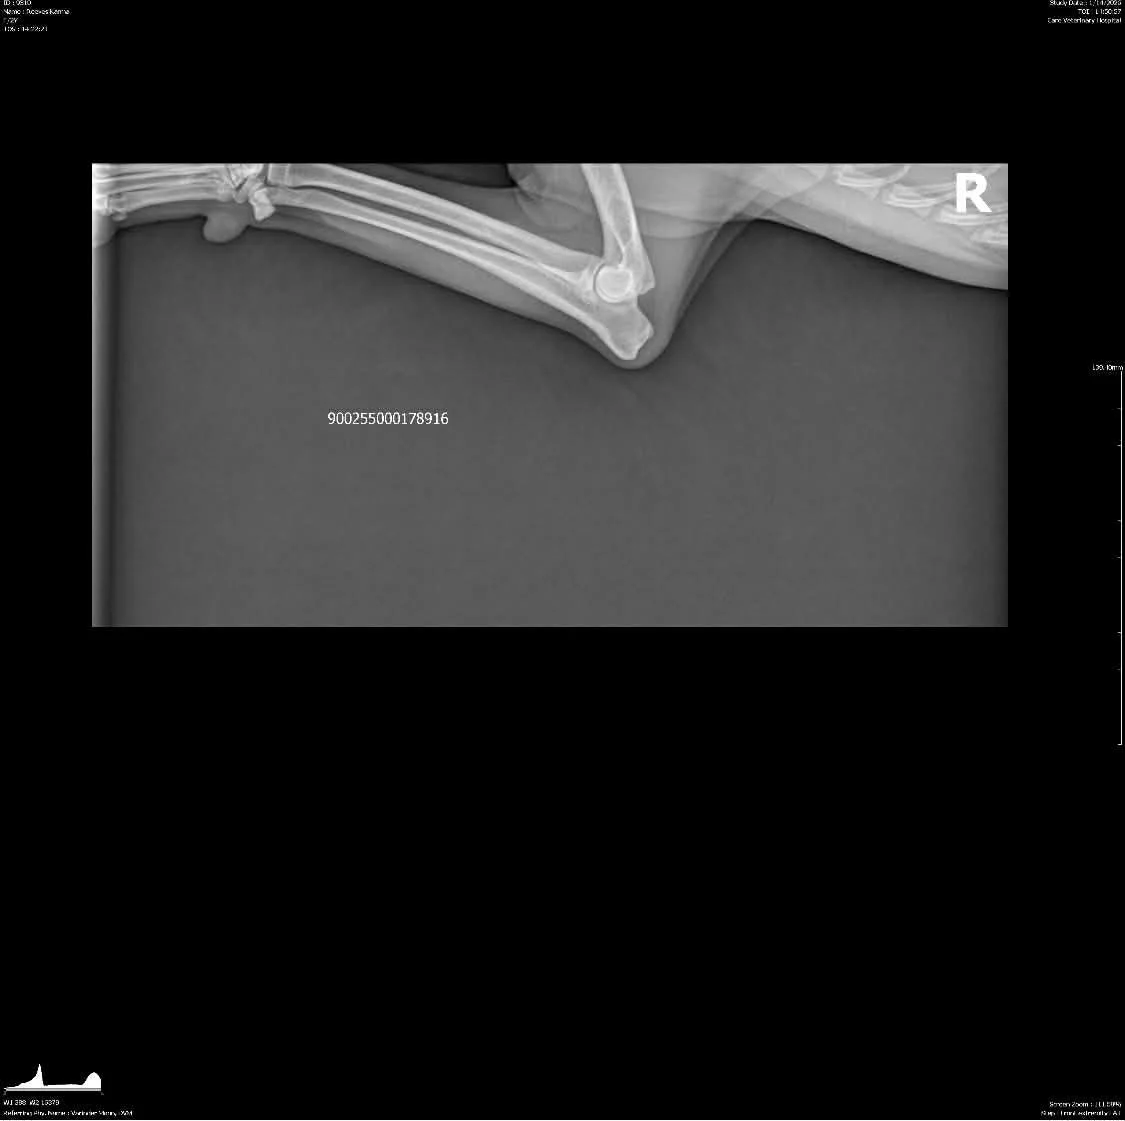

OFA Hips: Clear by parentage, scheduled for fall 2025

OFA Elbows: Clear by parentage, scheduled for fall 2025